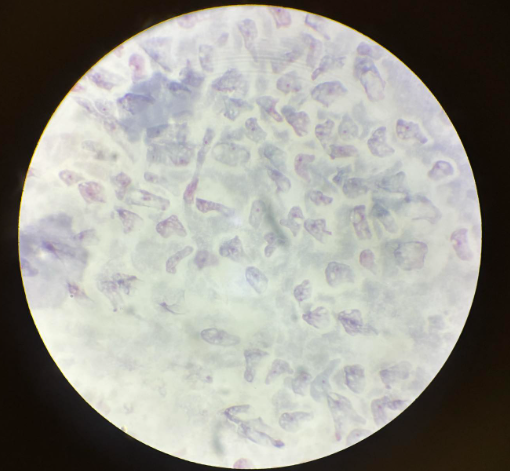

trypanosoma cruzi amastigota

trypanosoma cruzi trypomastigota